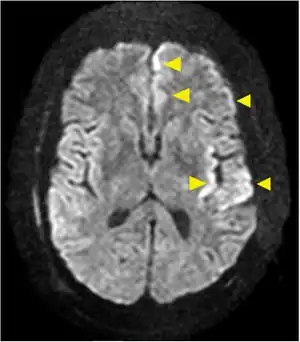

About 2 days to 2 weeks after the bite of an infected mosquito, disease symptoms of a nonspecific summertime illness with sore throat, runny nose and cough, followed by fever, headache, nausea and vomiting can develop. Many cases are asymptomatic, although the ratio of symptomatic to asymptomatic cases is unknown.[1] Neuroinvasive disease occurs in two thirds of reported cases and is characterized by severe headache and neck stiffness as in meningitis or increasing lethargy and altered mental status up to coma as in meningoencephalitis. Roughly half of reported cases are hospitalized, but deaths from the virus are rare.[1] No acquisition from a blood transfusion has been reported.[2]